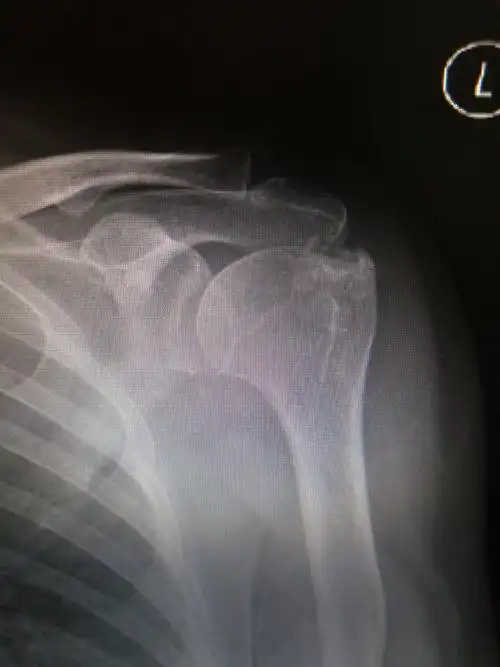

这是难见的肩关节损伤吧?

肩锁关节损伤

肩关节损伤的常见原因及处理

肩关节损伤

肩部骨折会有局限性疼痛,可导致肢体功能完全丧失,并发症有休克